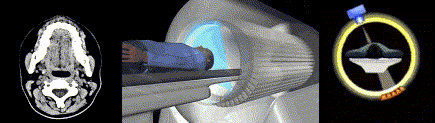

Компьютерная томография (КТ)

В 1972 году был получен первый цифровой срез живого головного мозга методом компьютерной томографии (КТ) (рис. 19А). Этот метод воплотился в реальность благодаря совместным усилиям Годфри Хаунсфилда и физика Аллана Кормака, которые учли при разработке прибора все предыдущие попытки ученых математически обосновать и экспериментально доказать возможность послойного построения трехмерного изображения тела и подсчета плотности тканей с помощью множества рентгеновских снимков, полученных под разными углами при вращении рентгеновской трубки вокруг тела пациента. Первые компьютерные томографы имели разрешение лишь 80⨉80 3-миллиметровых пикселей, а реконструкция одного изображения занимала 15 минут. Сейчас КТ-сканирование головного мозга с разрешением 512⨉512 пикселей занимает секунды (рис. 19Б). В 1979 году Хаунсфилд и Кормак стали нобелевскими лауреатами. Их разработка произвела фурор в медицинском сообществе [72].

Разработка альтернативных проектов по формированию цифровых изображений продолжалась. Дело в том, что компьютерная томография, основанная на рентгене, дает потенциально вредную лучевую нагрузку, а КТ-изображения мягких тканей, в том числе мозговых, неконтрастны, а потому мелкие структуры (например, подкорковые ядра, элементы ствола головного мозга, микроинсульты, очаги рассеянного склероза и т.д.) изучать сложно.

Магнитно-резонансная томография (МРТ)

Очень скоро в визуализацию мозга вмешались химики. В 1973 году американский химик Пол Лотербур предложил использовать явление ядерного магнитного резонанса (ЯМР), активно применяемого в расшифровке химической структуры молекул, для построения цифровых изображений. Ряд ученых, в том числе отечественных, уже высказывали эту идею ранее, но по иронии судьбы им всем, включая Лютербура, не выделяли государственного финансирования на разработку прибора, настолько фантастически-невозможным казалось воплощение идеи. Однако Лотербуру удалось впервые получить на своем приборе ЯМР-изображения (рис. 20А). Далее английский физик Питер Мэнсфилд усовершенствовал математические алгоритмы преобразования ЯМР-спектров в цифровое изображение. Мэнсфилд «не пощадил живота своего» — за полчаса он просканировал на приборе свою брюшную полость, чтобы убедить всех, что его метод эффективен и безопасен. С 1982 г. началось коммерческое производство ЯМР-томографов. После аварии на Чернобыльской атомной электростанции в 1986 г. ЯМР-томографы стали называть просто магнитно-резонансными томографами или МРТ, чтобы не пугать людей — ведь метод не дает лучевой нагрузки, в отличие от КТ (рис. 20Б). В 2003 году П. Лотербуру и П. Мэнсфилду была присуждена Нобелевская премия [73].